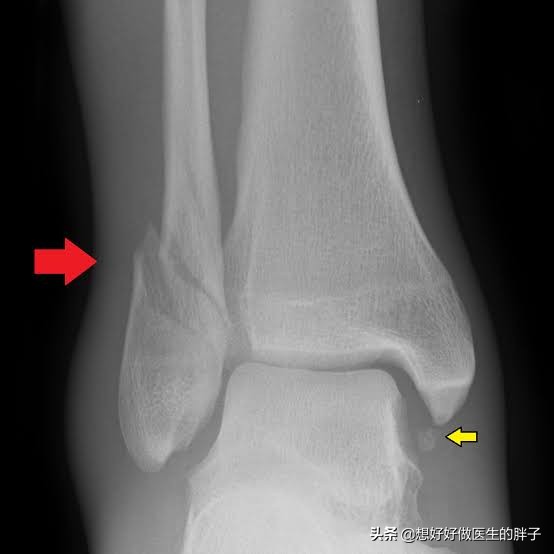

腓骨远端的螺旋骨折

在踝关节的损伤当中,有一种情况叫螺旋骨折,这种骨折在踝关节扭伤当中非常的常见。在损伤当时拍x线的时候,通常情况下骨折离断的并不是特别的明显,整体形态看着还可以,所以很多人采取了保守治疗。但是x线检查通常是平面的检查,它并不能代替整个三维情况的表现,一些螺旋骨折的患者往往需要进行手术治疗,因为这种骨折不是属于稳定骨折,很有可能保守治疗效果不好,骨折断裂的距离会越来越大。

如果是这种情况导致三个月的时间踝关节还疼,应该复查x线,明确骨折恢复的情况,此时已经错过了最佳的治疗时间,如果强行手术将已经形成骨痂的部分重新打开,将会造成比较大的创伤。所以如果不是情非得已还是要考虑进行保守治疗,如果疼痛比较明显,可以口服或者是外用一些镇痛药物帮助控制疼痛,要加强踝关节的康复锻炼。尽量的减少长时间的负重行走,给踝关节一个恢复的机会,有的时候症状慢慢的就会消失掉。